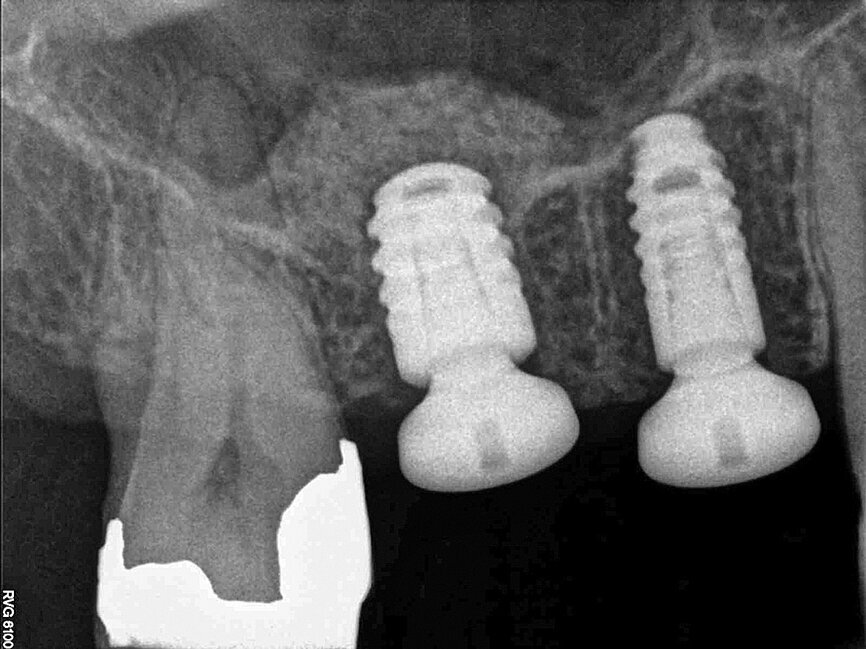

Fig. 19: Computer-guided navigation enabled the implants to be placed reliably and predictably within optimum bone, without the need to reflect a flap.

The scan was taken with a Morita 3-D CBCT system, which provides high definition, distortion-free images for accurate diagnosis and planning. Radiographic and CBCT examination revealed approximately 9 mm of bone depth, from the crest of the ridge to the floor of the maxillary antrum, in the upper right second premolar site, and no more than 5 mm bone depth in the first molar site. Planning took place immediately after the scan, with the patient present, so she could see the proposed treatment on the Navident software. She felt reassured by the care being taken to achieve optimum implant positioning, with minimal risk of potential complications, and was extremely impressed with the technology.

A 3.5 mm diameter and 8 mm length Dentsply Ankylos C/X implant was placed 1 mm subcrestally in the upper right second premolar site. A guide pin was placed in the upper right first molar site to check the depth and alignment (Fig. 11). The NaviStent was removed and the site was prepared for the sinus lift osteotome (Figs. 12 and 13). The osteotome was tapped gently with a surgical mallet until the remaining thin layer of bone infractured and was elevated (Fig. 14). The Schneiderian membrane was carefully raised through manipulation with the osteotome and a heterogeneous bovine bone graft material (Bio-Oss, Geistlich) was introduced into the implant site (Fig. 15). A 4.5 mm diameter and 6.6 mm length Ankylos C/X implant was then placed 1 mm subcrestally (Figs. 16 and 17). Both implants had good primary stability on placement. Ankylos Balance posterior sulcus formers were fitted, without the need for additional closure with sutures (Fig. 18).

Navident was used to guide the implant site preparation dynamically, to ensure implants were placed in the pre-determined position without the need for a static drilling guide. This facilitated placement of the implants in the optimum amount of bone without inadvertent damage to the maxillary sinus membrane. It also ensured that their alignment made future impression taking and restoration straightforward. The ability to watch the drill virtually on the CBCT scan, as the implant sites were prepared, allowed the exact point at which to cease vertical drilling to be judged visually.

Computer-guided navigation enabled the implants to be placed reliably and predictably within optimum bone, without the need to reflect a flap (Fig. 19). Consequently, the patient experienced no postoperative swelling or bruising and she reported very little discomfort after treatment. This outcome satisfied the primary objective of aiming for clinical perfection, whilst ensuring the patient experienced the least trauma possible.